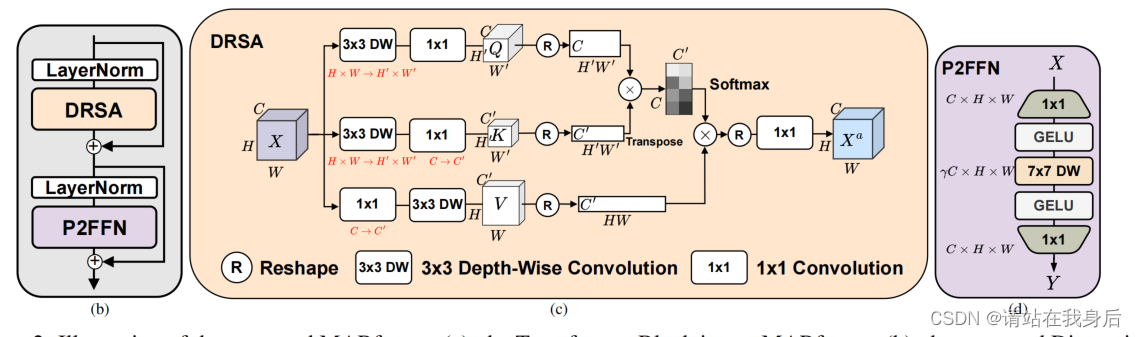

每个变压器块由DRSA和P2FFN组成

DRSA模块的目标是对高分辨率特征图进行有效的自关注。首先沿着通道维度计算全局相似矩阵,通过DW卷积将数据投影到注意力机制需要用到的Q\K\V,然后计算获得注意力得分,后面的reshape操作是因为医学图dcm一般很小,因此进行一定程度的转换。总体来说就是一个注意力

P2FFN模块是由一个1×1扩大频道维度从C到γC, GELU激活函数,一个深度方面7×7卷积GELU感知局部图像,而另一个1×1卷积缩减渠道维度从γC 到C。